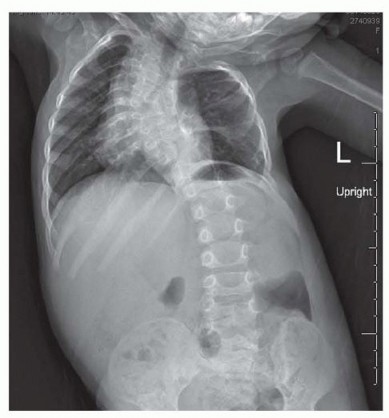

Pelvic Fixation for Neuromuscular Scoliosis DEFINITION Neuromuscular scoliosis (NMS) is a spinal deformity in…

Spinal Fusion for Neuromuscular Scoliosis DEFINITION Neuromuscular diseases are heterogeneous between and wit…